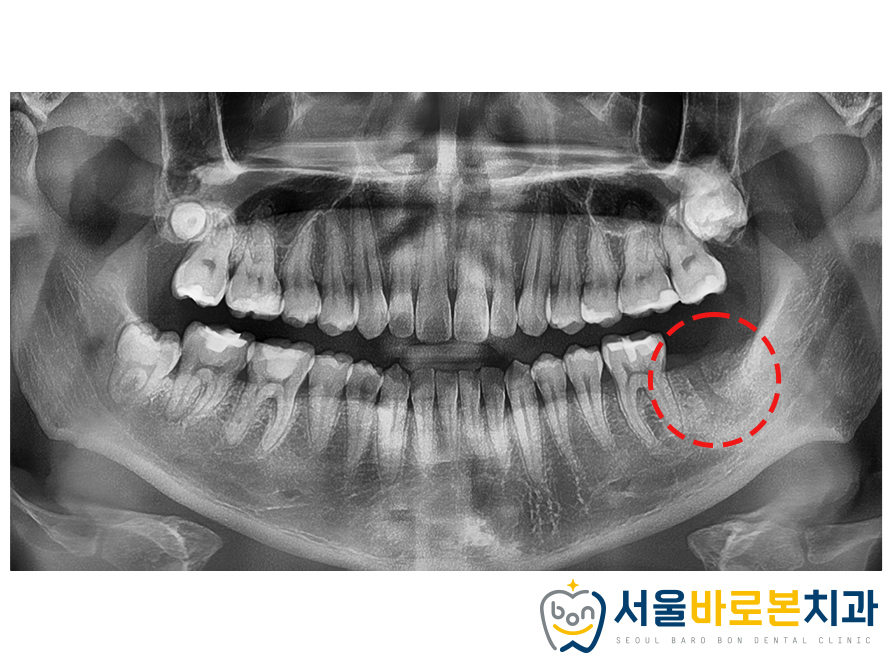

발치를 진행하고,

치아를 뽑은 자리(발치와)가 잘 아물고

뼈가 잘 재생될 수 있게 보존해 주는

발치와 보존술을 시행해주었습니다.

뼈가 잘 회복되고 나면

임플란트 수술을 진행하기로

환자분께도 설명을 드렸는데요.